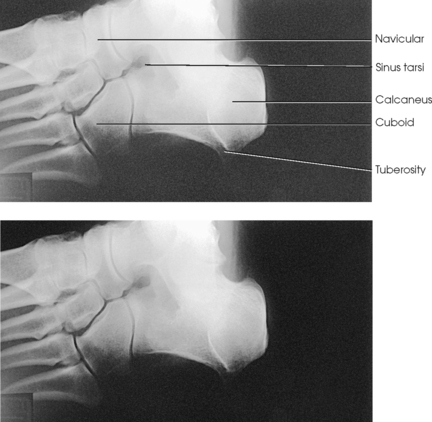

Structures shown: The resulting image shows the interspaces between the following: the cuboid and the calcaneus, the cuboid and the fourth and fifth metatarsals, the cuboid and the lateral cuneiform, and the talus and the navicular bone. The cuboid is shown in profile. The sinus tarsi is also well shown (Fig. 6-47).

Structures shown: The resulting image shows an AP (dorsoplantar) projection of the tarsals anterior to the talus, metatarsals, and phalanges (Figs. 6-43 to 6-45). This projection is used for localizing foreign bodies, determining the location of fragments in fractures of the metatarsals and anterior tarsals, and performing general surveys of the bones of the foot.